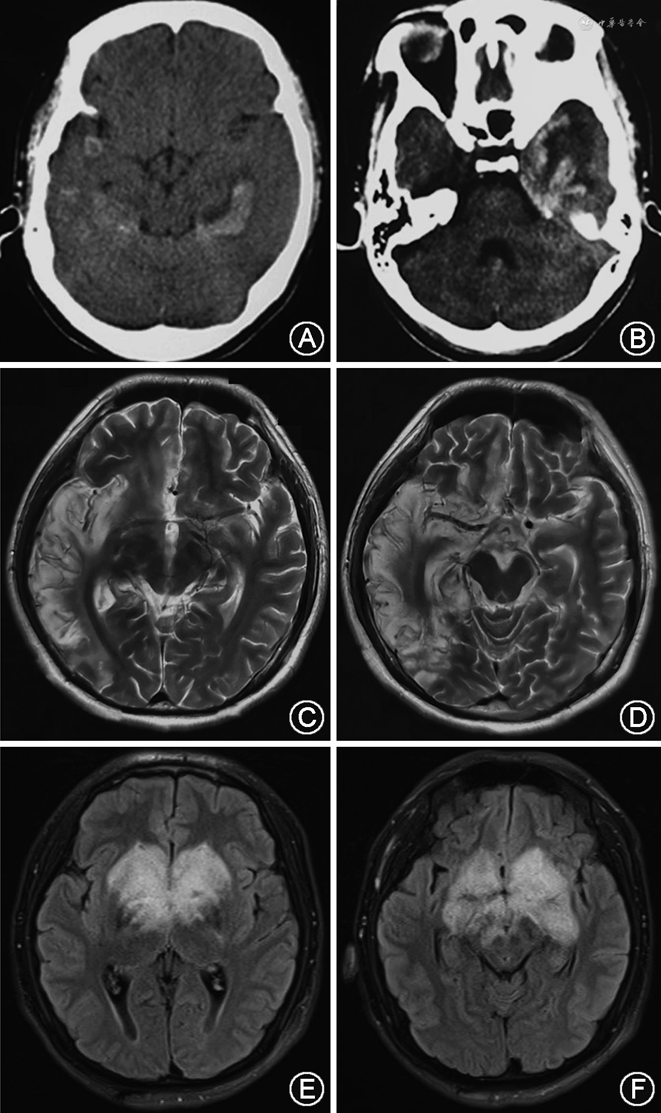

1.HSE:HSE主要由HSV-1引起,在成人病毒性脑炎中,HSE是最常见的一种。HSV-1又称人类疱疹病毒1型,为双链DNA病毒,HSE的主要病理改变为边缘系统的出血坏死性炎症。HSE可发生于任何年龄,呈散发性,无明显的季节性和地域性特征,少数患者可有口唇疱疹病史。临床急性起病,表现为发热、头痛、癫痫发作、精神行为异常、认知功能与近记忆力障碍,部分患者出现局灶性神经症状(偏瘫、失语等)。症状可进行性加重,出现意识障碍和昏迷。辅助检查:(1)脑脊液压力正常或升高,白细胞增多(5×106/L~500×106/L),以淋巴细胞为主,亦可有红细胞轻度增多,蛋白水平升高,葡萄糖含量正常。(2)脑电图:可见弥漫性高波幅慢波,以单侧或双侧颞、额区异常为主,可出现颞区的尖波及棘波。(3)影像学:头颅CT可见病变主要位于边缘系统,以颞叶受累常见,呈低密度改变,有时可见出血;MRI显示边缘系统病变,单侧或两侧颞叶底面和内侧面、下额叶、岛叶等部位长T1、长T2异常信号,增强MRI可见脑回强化,可有出血性改变(图1)。(4)确诊实验:脑脊液病毒核酸检测,包括PCR与mNGS法;脑活组织检查的免疫组织化学与核酸检测也可用于确诊。

3.流行性乙型脑炎:简称乙脑,又称日本脑炎,乙脑病毒属于单正链RNA病毒、黄病毒属。人与多种牲畜、禽鸟类均可感染乙脑病毒,猪是乙脑病毒的主要传染源,经蚊虫叮咬传播。乙脑累及整个CNS的灰质,以基底核、丘脑和大脑皮质最严重,脊髓灰质也可受累。本病主要出现于夏、秋季,轻症患者表现为脑膜炎或者单纯的精神行为异常;重症者以抽搐、意识障碍、呼吸衰竭为主要表现;累及脊髓灰质者,可表现为急性弛缓性麻痹,出现1个或多个肢体瘫痪,下肢较上肢明显。近年我国西北地区乙脑以成人和老年患者为主,且可引起吉兰-巴雷综合征样表现,包括急性运动轴索性神经病和急性感觉运动轴索性神经病[15]。患者的脑脊液白细胞计数多在50×106/L~500×106/L,早期以中性粒细胞为主,后逐渐转变为淋巴细胞为主的炎症。头颅MRI显示双侧丘脑、基底节、脑干受累,有或无异常强化,有时也可见小脑、脊髓和大脑皮质异常信号,部分患者头颅MRI正常(图1)。确诊实验首选抗乙脑病毒抗体(IgM)检测;脑脊液或血液PCR检测乙脑病毒核酸阳性可以确诊。